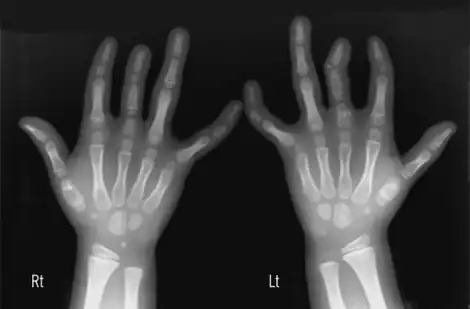

| Different forms of brachydactyly | |

Brachydactyly (Greek βραχύς = "short" plus δάκτυλος = "finger"), is a medical term which literally means "short finger". The shortness is relative to the length of other long bones and other parts of the body. Brachydactyly is an inherited, usually dominant trait. It most often occurs as an isolated dysmelia, but can also occur with other anomalies as part of many congenital syndromes. Brachydactyly can also be a signal that one will be at risk for heart problems as they age.